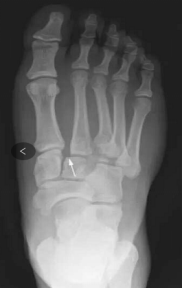

痛风

嘌呤代谢紊乱,以体液、血液中尿酸增加及尿酸盐沉着于各种间叶组织内引起炎症反应

好发于男性,发病高峰40-60岁

以第1跖趾关节最为多见

早期周围软组织肿胀,出现局限骨质硬化,晚期关节面边缘出现囊状、穿凿状骨质缺损,关节间隙可变窄,关节面不光整,晚期骨赘形成可使骨端增大

68Y,M